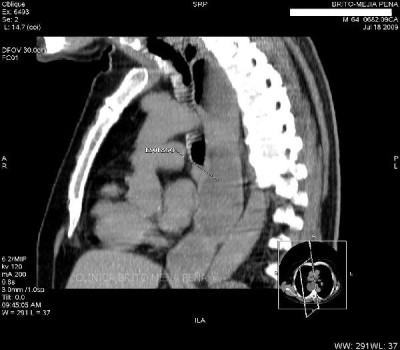

Masa esofágica sagital